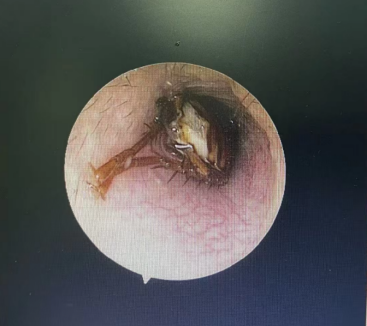

转诊后,耳鼻咽喉头颈外科医生用电耳镜进行观察,发现一只蟑螂卡在外耳道深处,进退不得。金先生一直喊疼,并说感觉到耳道内物体的活动。”

不久后,确认蟑螂已被处死,金先生疼痛暂时缓解,大清早又赶紧去做耳内镜,医生最终用镊子从金先生外耳道取出了指甲盖大小的蟑螂,并为他进行耳道消毒。

取出虫子前